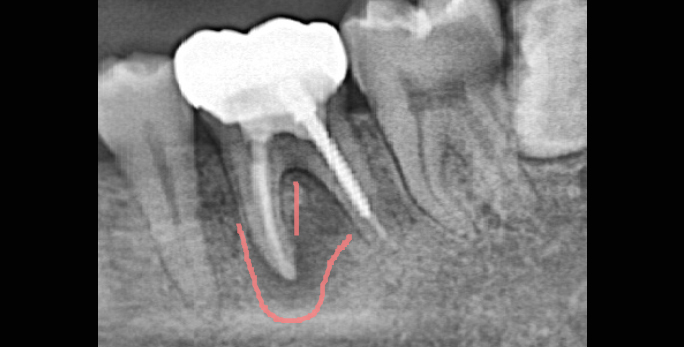

• 신경치료한 뿌리 끝에 염증이 크게 번져있는 상태 치료 후 염증 및 통증 소실